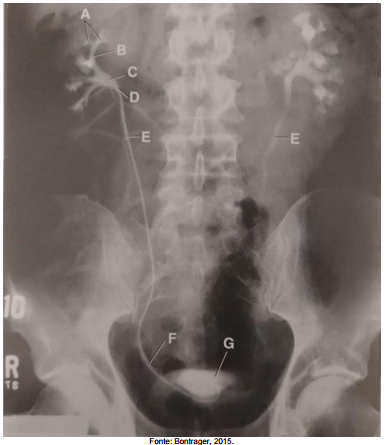

Analise a figura a seguir, que apresenta uma imagem de uma pielografia retrógrada

(cateter no ureter direito).

Assinale a alternativa que apresenta a correta correlação entre a indicação e a estrutura na imagem tomográfica.